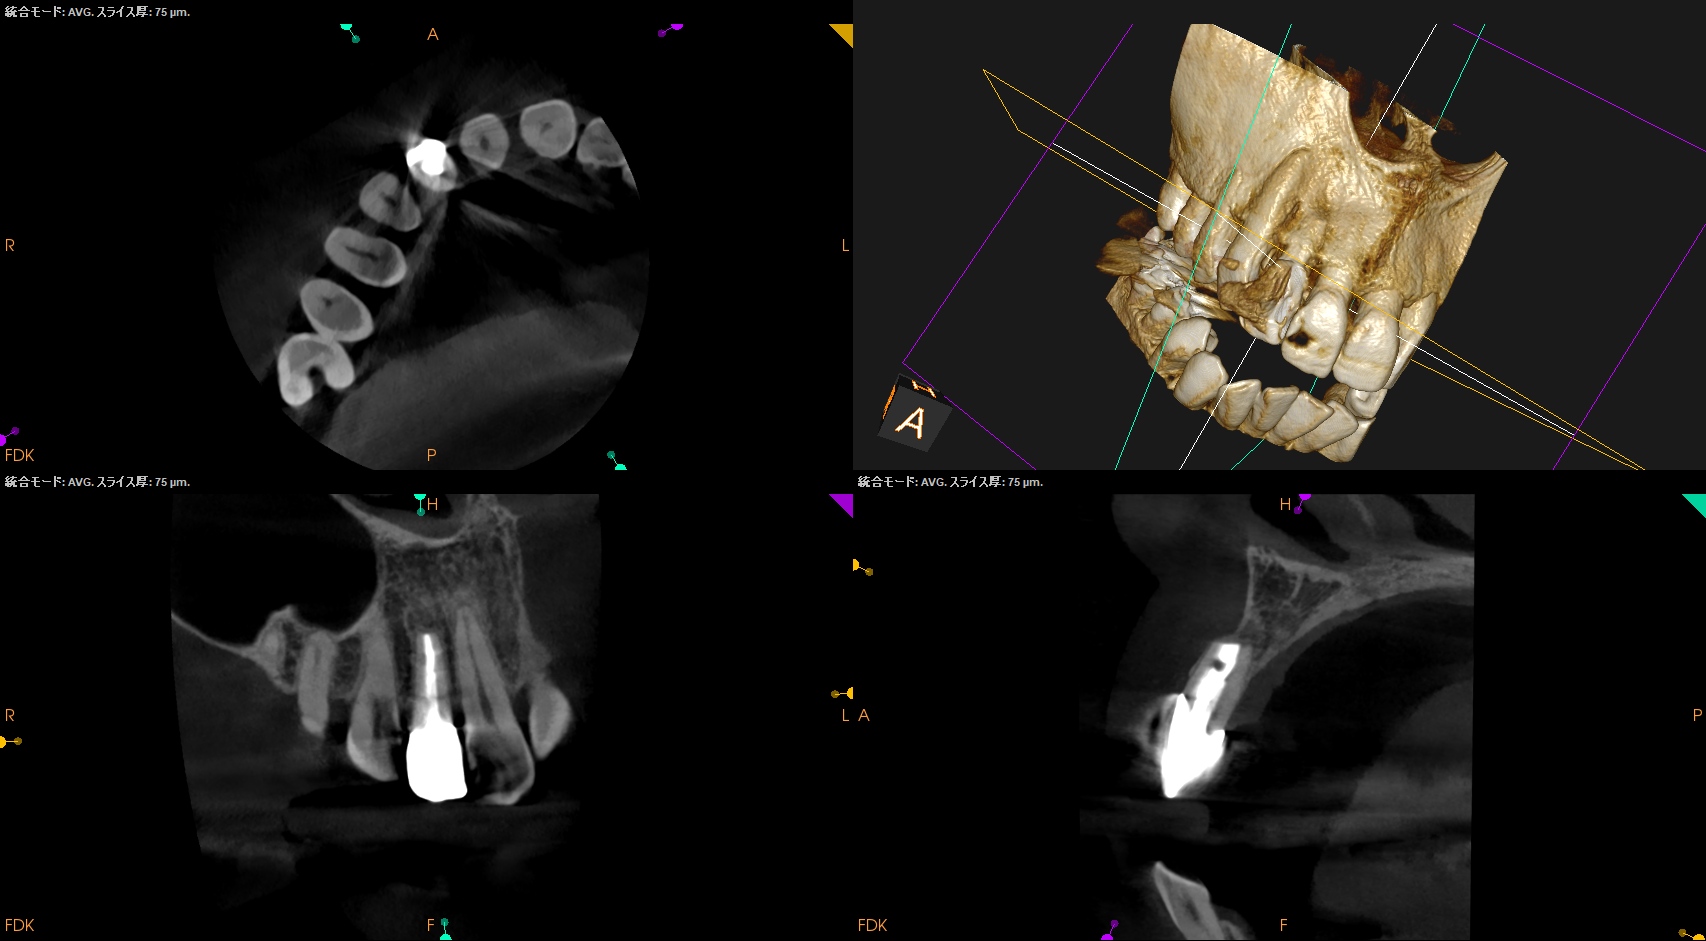

根尖が既に開いており、圧痛があったことから治療は再根管治療ではなく、歯根端切除術であるということがわかる。

その際は、

クラウンのマージンより11.5mm下方に#7のApexはあり、そこを3mm切断するには頬舌的に4.4mmの幅があるということがわかる。

実にEasyなApicoectomyだ。

術後にPA, CBCTを撮影した。

初診時と比較した。

気泡は入ったが劇的に治癒し、臨床症状もないことからこの日で終診となった。